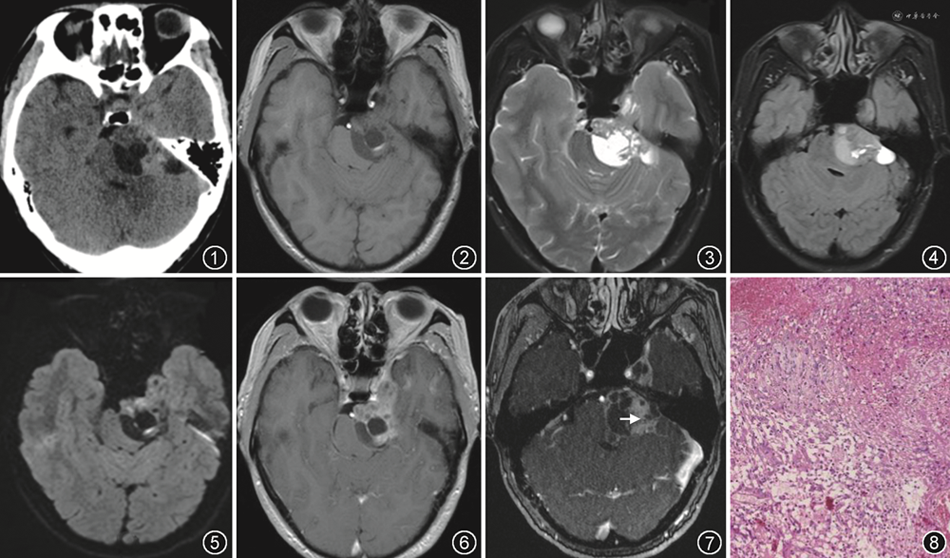

患者 男性,43岁。因突发头晕3 d,加重伴左耳鸣、左耳听力较前明显下降、步态不稳1 d入院。体检:醉酒样步态,活动后感眩晕,平衡障碍。闭目难立征:欠稳,Rinne试验:AC>BC,Weber试验:偏右。患者无呕吐、无眼球震颤。CT平扫:左侧桥小脑角(cerebellopontine angle,CPA)区见混杂密度不规则肿块(图1)。MR检查:左侧中后颅窝-CPA区见大小约47 mm×41 mm的囊实性占位肿块,T1WI以低信号为主,内见类圆更低信号区及点线状高信号;T2WI呈等高混杂信号,液体衰减反转恢复序列呈等高混杂信号(图2~4);DWI示部分病灶呈高信号,ADC减低,病灶与左侧听神经关系密切,向前跨中颅窝生长,左侧三叉神经结构显示不清,病灶向右压迫脑干及桥臂(图5)。增强MRI示病灶明显不均匀强化(图6),MRA可见病灶内迂曲小血管影(图7)。MR诊断:三叉神经鞘瘤可能。遂行左侧CPA直切口开颅肿瘤切除术。术中沿小脑外侧探查CPA,肿瘤位于CPA,根部附着左侧三叉神经,呈实性、灰白色,质地软,血运极丰富,无薄膜,与周围界限欠清,与脑干粘连紧密。小脑前下动脉与肿瘤表面粘连紧密,面、听神经被肿瘤包裹。术后病理:病灶内大片出血,可见肿瘤细胞密集,核浆比例较高,肿瘤细胞呈上皮样排列,细胞大小不一,异形程度不等,并可见瘤巨细胞及病理性核分裂象,部分细胞呈空泡状并含有红细胞(图8)。免疫组化:CD31(+),波形蛋白(+),CK灶(+),EMA灶(+),CD68灶(+),CD34(-),SYN(-),Olig-(-),S100(-),GFAP(-),CgA(-),PR(-),SOX10(-),D2-40(+),Cam5.2(+),抑制素α(-),Ki-67 5%~8%(+)。诊断为上皮样血管内皮瘤(epithelioid hemangioendothelioma,EHE)。

由于EHE的瘤内组织间含有丰富的血窦伴少量出血,因此CT多呈稍高密度表现。此外,因EHE内细胞与黏液样基质成分多变,故MR表现常多种多样[5]。该例患者病灶呈混杂信号伴少量出血,囊变明显,增强后呈不均匀强化,实性部分及囊壁强化,囊性部分无强化,病灶跨中后颅窝生长,并同时累及Meckel腔,因此术前被误诊为三叉神经鞘瘤。MRA示病灶可见异常血管,与Tian等[5]发现相似,这可能解释了该肿瘤富血供的特征。然而,与夏建国等[6]报道不同,本例患者病灶的实性成分局部呈轻度扩散受限,可能与病理镜下可见局部肿瘤细胞密集,核浆比例较高有关。

总之,颅内EHE罕见,影像上具有一定特点:病灶易出血、囊变,信号不均,肿瘤实性部分T2WI多呈中等偏高信号,DWI示无或轻度扩散受限,增强后不均匀强化,MRA示病灶内可见异常供血动脉。因EHE低度恶性和血供丰富特点,会明显影响手术和预后,故应作为颅内脑外,特别是CPA占位病变的鉴别诊断选项。